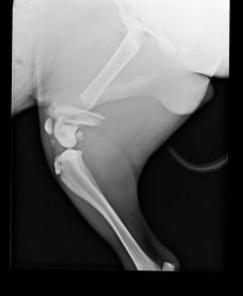

La radiographie est l’un des outils utiles en imagerie médicale. Chez les animaux, comme chez les humains, les radiographies permettent de visualiser certaines parties du corps comme le cœur, les poumons, les intestins ou encore les os.

La plupart des radiographies peuvent être réalisées rapidement mais d’autres nécessitent des tranquillisations de courtes durées car votre animal ne doit pas bouger. On distingue les utilisations suivantes de l’appareil radiologique :

- Radiographies des membres : pour la recherche de fractures mais également l’évaluation de différents problèmes articulaires comme l’arthrose ou la dysplasie.

Appareil de radiographie

Nous disposons d’un équipement de radiographie numérique, permettant d’avoir des clichés de votre animal en quelques minutes.

Les radiographies sont d’un atout majeur dans le diagnostic de nombreuses pathologies (fractures, problèmes respiratoires, troubles digestifs …).